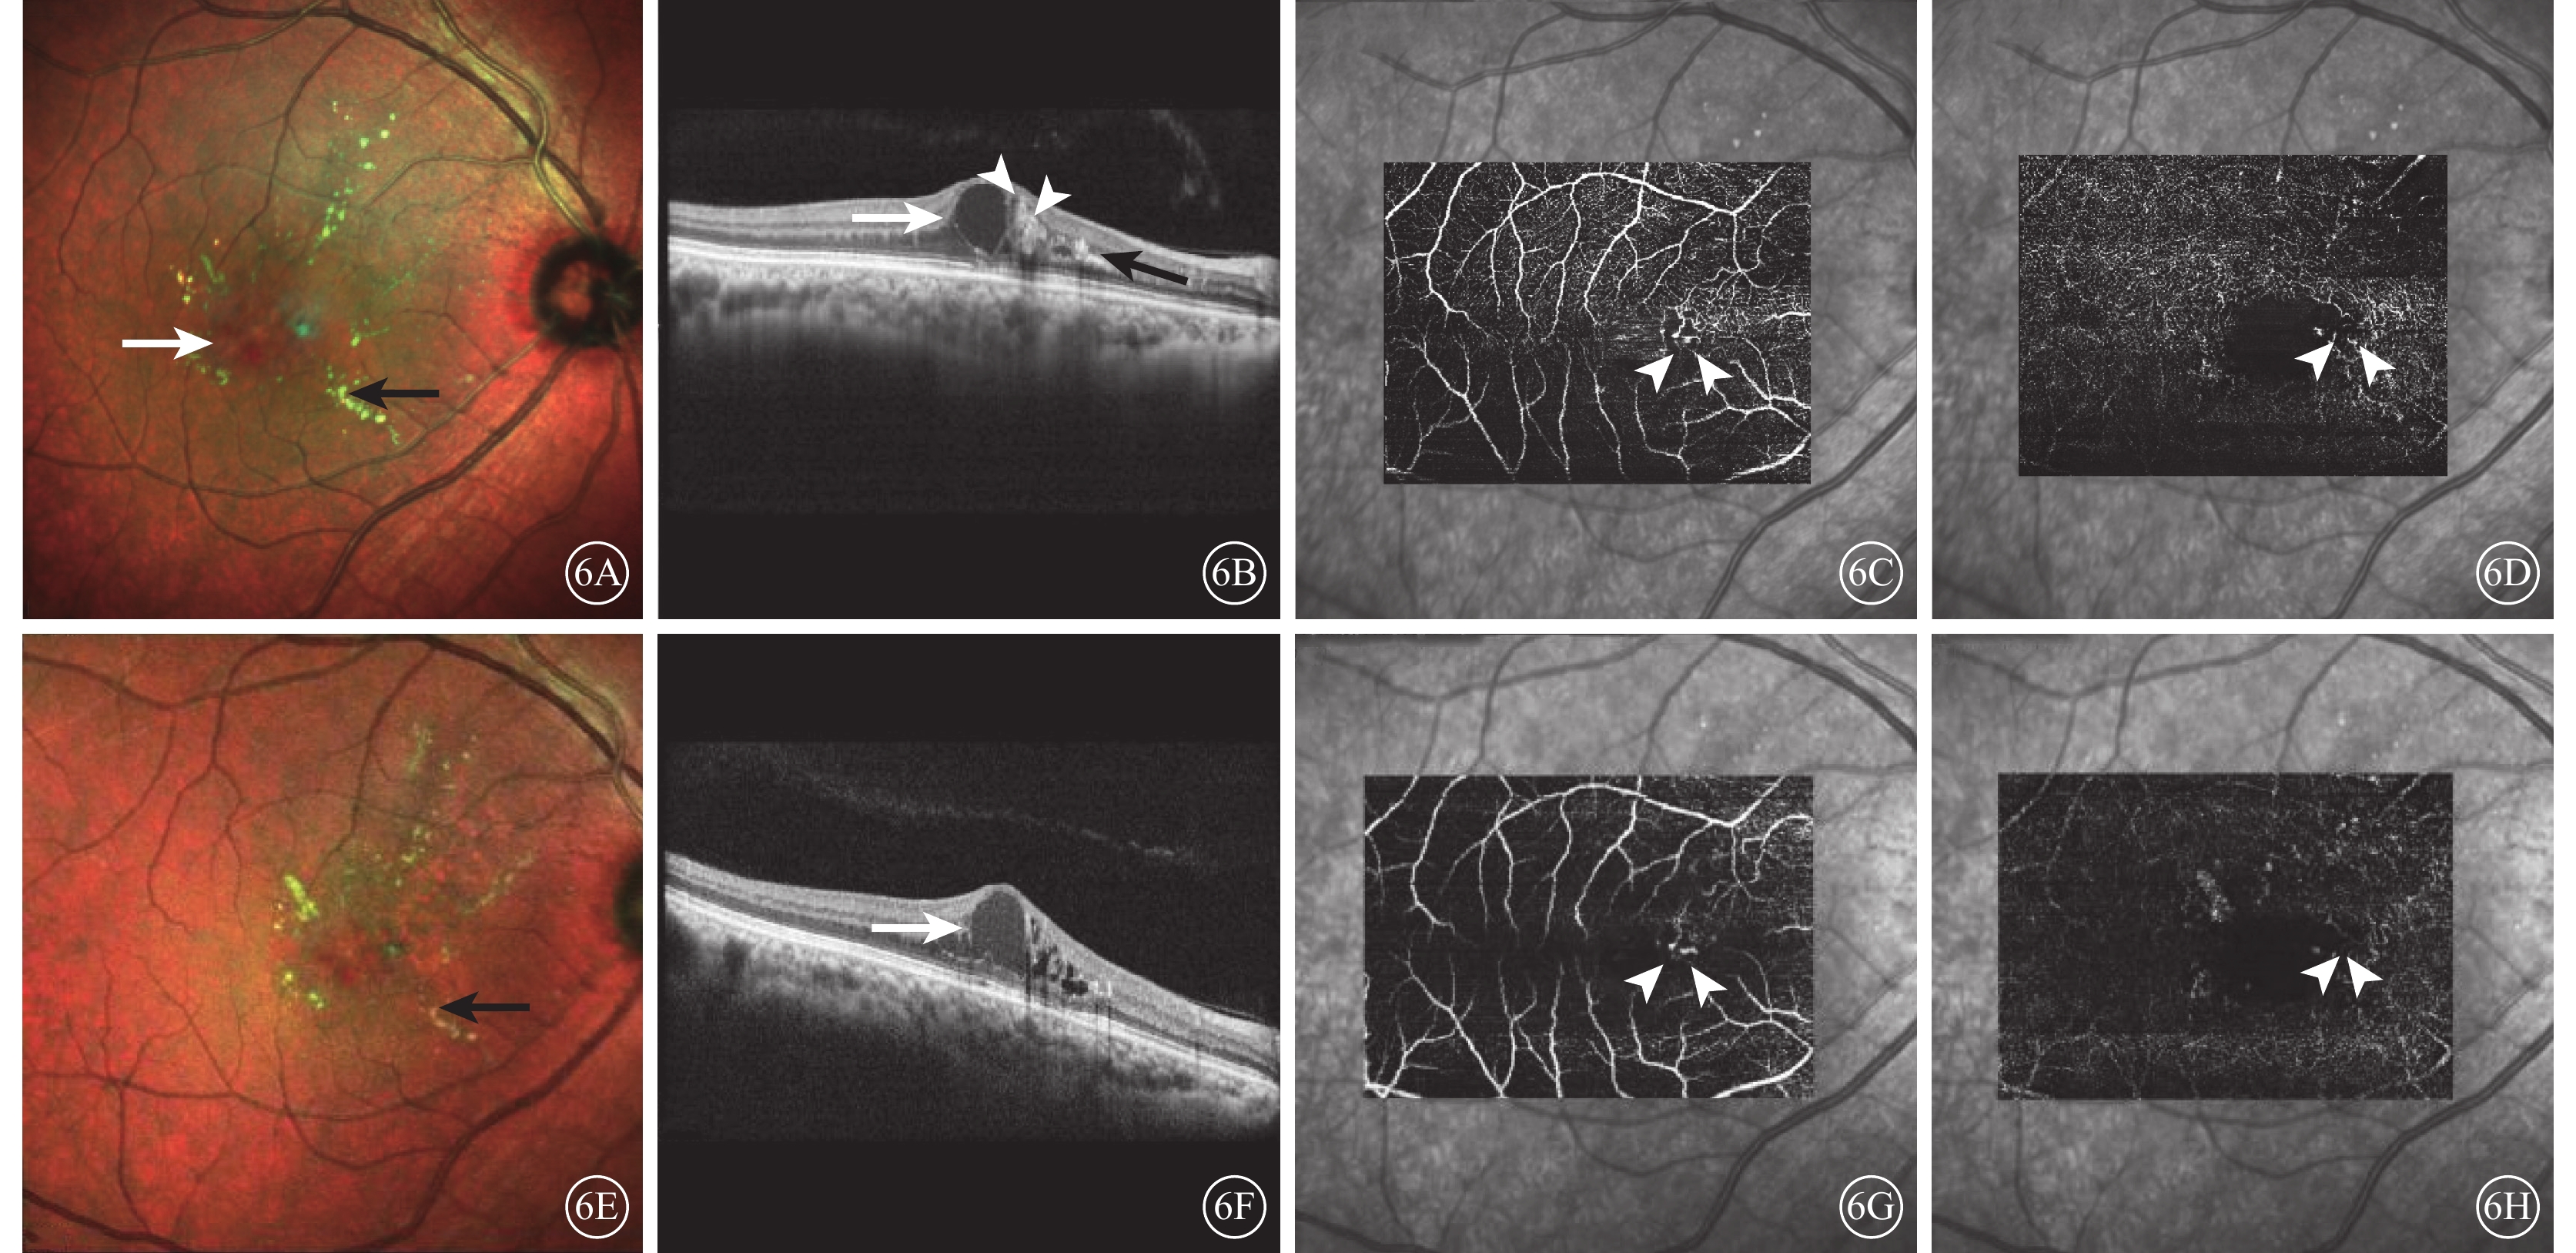

治療后完成隨訪的5只眼中,4只眼視網膜出血基本吸收,硬性滲出部分消退,CMT降低,中心凹神經上皮層間囊腔減小,瘤樣病灶范圍縮小(圖4),BCVA提高;1只眼硬性滲出略有增加,BCVA輕度降低。接受6次抗VEGF藥物治療(阿柏西普、雷珠單抗各3次)的1只眼,黃斑區視網膜下液及周圍硬性滲出均無明顯改善,其后給予病灶局部熱激光光凝治療。治療后瘤樣病灶內反射增加,與強反射壁邊界不清,視網膜下液及小囊腔逐漸消退,硬性滲出減少,CMT降低(圖5)。未行抗VEGF藥物治療的1只眼,給予熱激光光凝治療后2個月,黃斑區囊腔減小、硬性滲出部分吸收(圖6);治療后4個月,因情緒激動致血壓升高,病情復發,CMT增加。